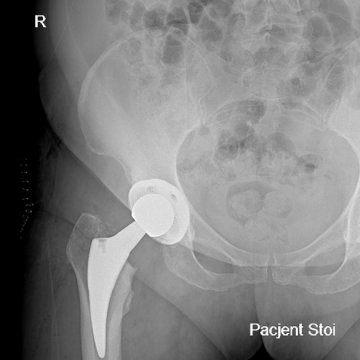

Jest to jeden z najbardziej zaawansowanych i precyzyjnych sposobów operacyjnego leczenia biodra, który pozwala na przeprowadzenie zabiegu bez przecinania mięśni, przez naturalne przestrzenie anatomiczne. Technika ta zyskuje coraz większe uznanie w leczeniu choroby zwyrodnieniowej stawu biodro wego, szczególnie wśród pacjentów poszukujących szybszego powrotu do aktywności.

niższe ryzyko powikłań i zwichnięć protezy

szybszy powrót do codziennej aktywności, również zawodowej i sportowej

Zabieg wykonuję z użyciem wysokiej jakości, nowoczesnych implantów dobieranych indywidualnie do budowy anatomicznej i potrzeb pacjenta. Całość leczenia opiera się na zasadach tzw. szybkiej ścieżki (fast-track), co oznacza także odpowiednio zaplanowaną rehabilitację i stały nadzór pooperacyjny. Dzięki takiemu podejściu, endoprotezoplastyka biodra w moim wykonaniu stanowi skuteczną i bezpieczną metodę leczenia zwyrodnienia stawu biodrowego – szczególnie dla pacjentów oczekujących szybkiego powrotu do sprawności.

Efektem jest sprawne, bezpieczne i przewidywalne leczenie, które pozwala pacjentom odzyskać komfort życia Jeśli rozważasz leczenie operacyjne stawu biodrowego i interesuje Cię nowoczesna, małoinwazyjna technika MIS DAA, zapraszam na konsultację ortopedyczną.